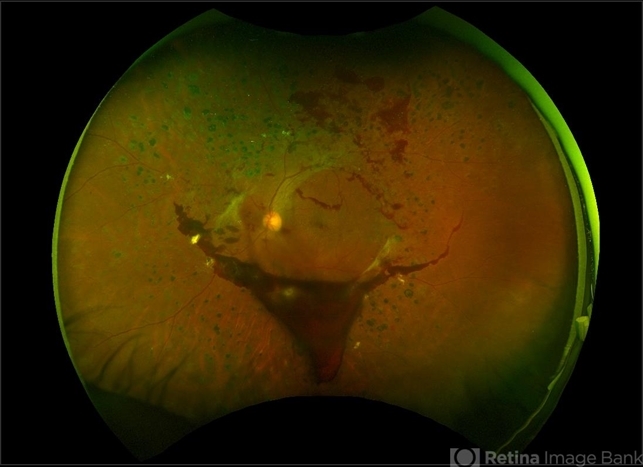

- proliferative diabetic retinopathy (PDR), diabetic mellitus, Optos, ultra-wide field imaging, hemorrhage, neovascularization (NV), color fundus photograph, left eye, pseudocolor

- Ultra-wide field pseudo-color image of an 57-year-old male with a large pre-retinal hemorrhage secondary to proliferative diabetic retinopathy affecting his left eye.